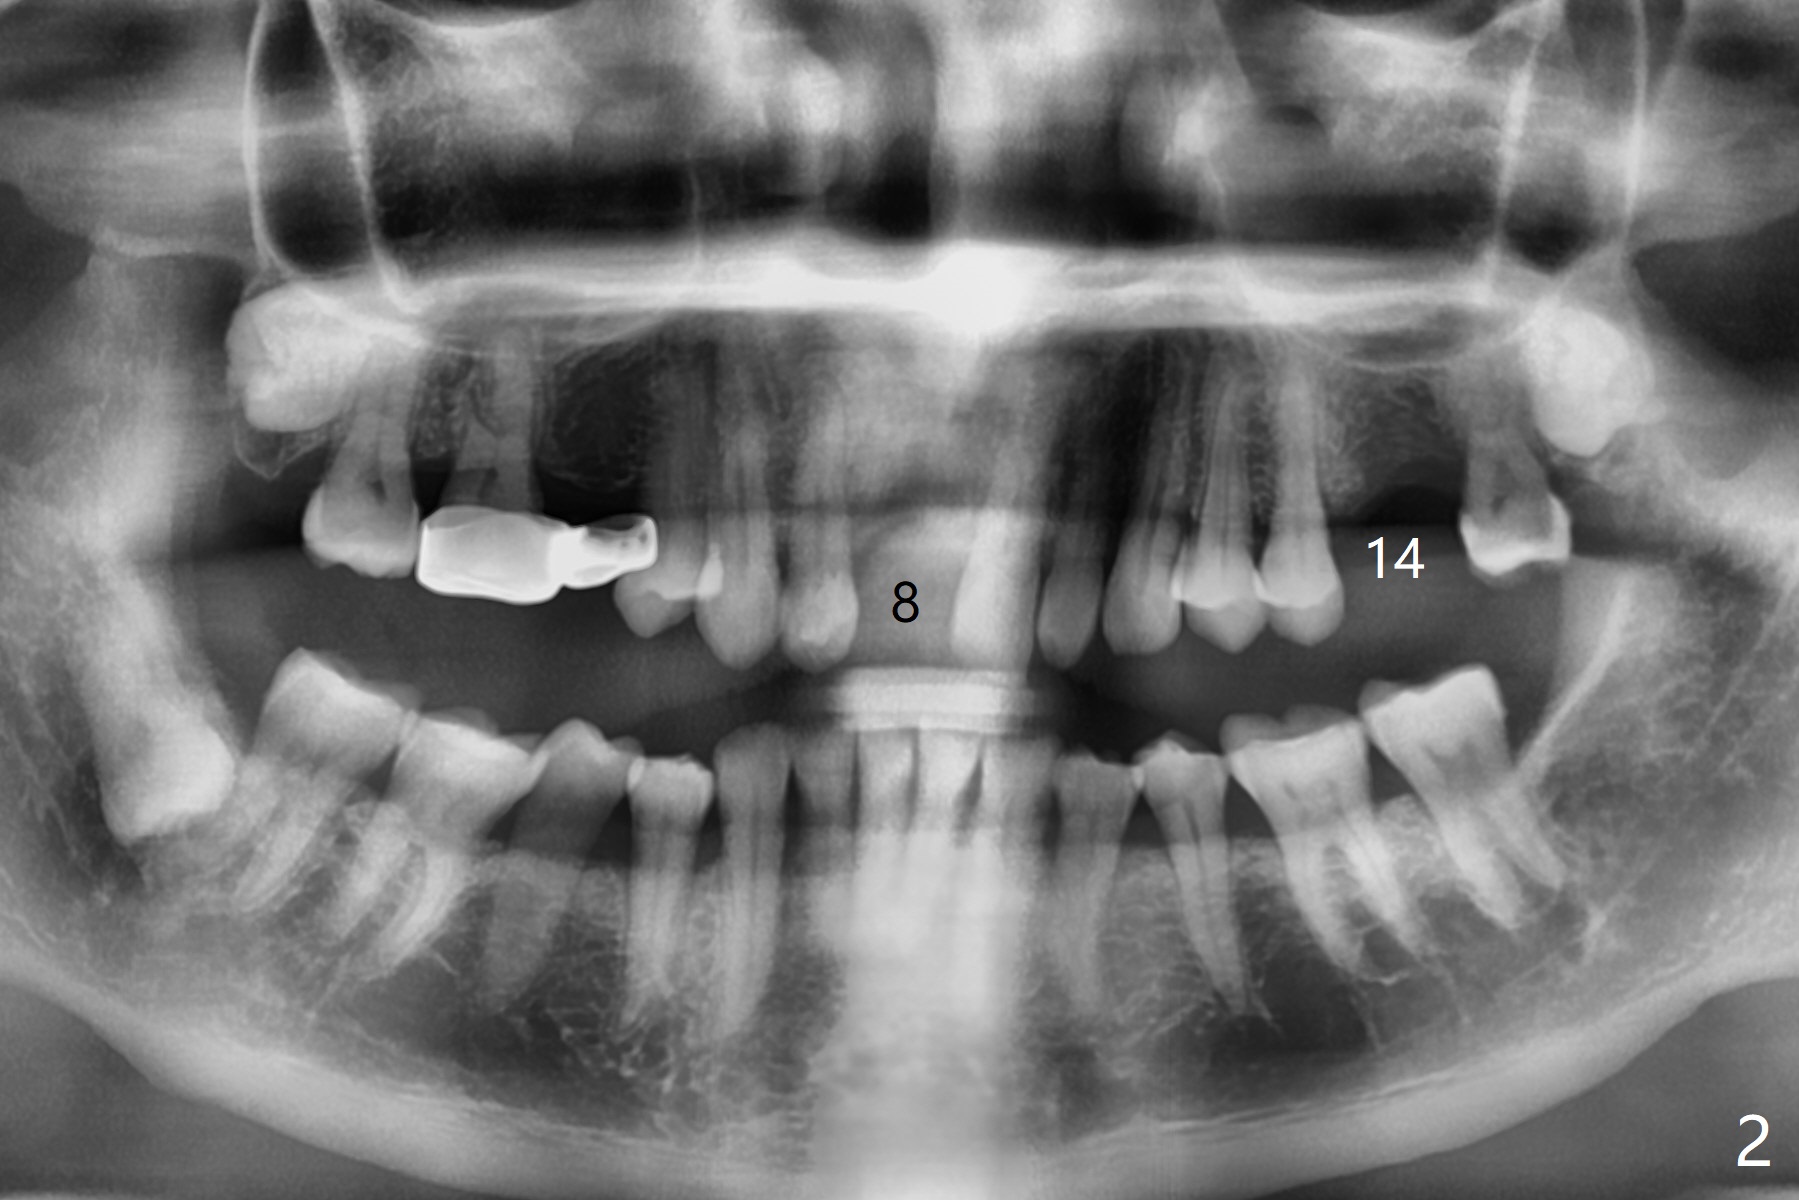

A 69-year-old man (ex-soldier) had the tooth #8 extracted for a flipper nearly 8 years earlier (Fig.1 (obliterated canal)). A denture tooth is added at #14 after extraction in NY a few years later (Fig.2). In spite of sufficient bone width at #8, a 2.5x10 mm mini implant will be chosen to reduce the chance of palatal thread exposure (Fig.3 P). A 5x8.5 mm implant will be placed at #14 to achieve enough stability and not cause sinus complication (Fig.4). Take preop photos to show the anterior deep overbite and overjet. In fact the patient canceled the surgery. Two years later, he returns with history of right TMJ dislocation, which may be related to reduced mastication efficiency and partial edentulism (Fig.5,6).